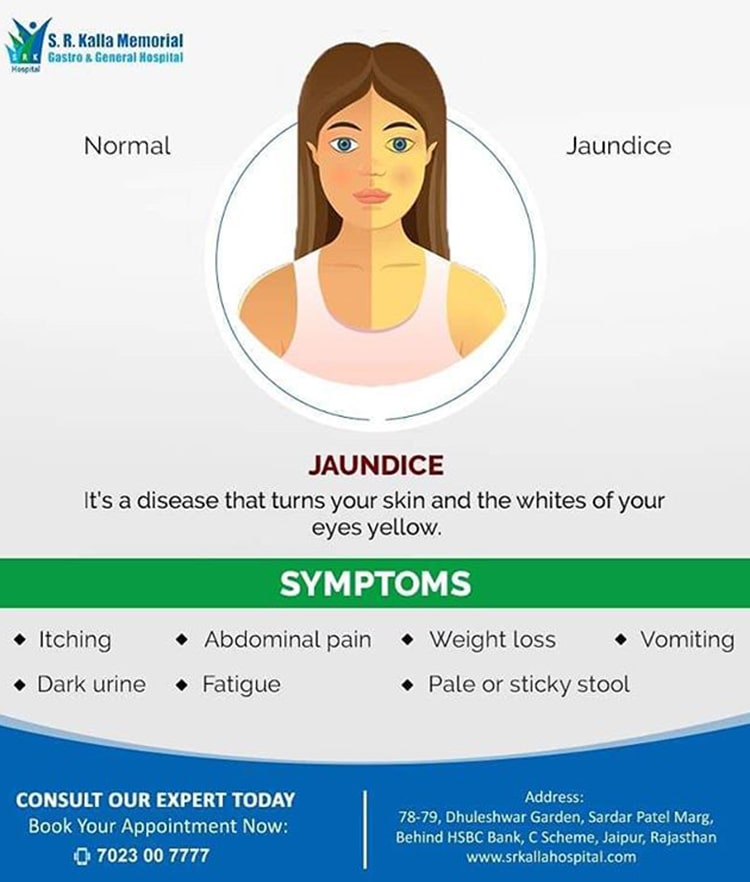

I had stomach pain and yellow color in my eyes. I was diagnosed to have Jaundice and gallbladder stones. I had to undergo the ERCP procedure and I must say I was very anxious. I would like to thank all staff, doctors, and helping staff for their care and treatment. I was discharged yesterday after the successful removal of stones.

My father was suffering from jaundice and pain in the stomach. He was diagnosed with multiple stones in gallbladder and liver. He was advised to undergo surgery which was difficult because of his heart condition. I found the Laser Lithotripsy procedure at SR Kalla Hospital. Thanks to doctors for treating my father and making him well.

Jaundice is caused by a buildup of bilirubin, a waste material, in the blood. An inflamed liver or obstructed bile duct can lead to jaundice, as well as other underlying conditions. Symptoms include a yellow tinge to the skin and whites of the eyes, dark urine, and itchiness.